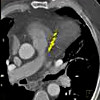

КТ коронарного кальция. Дополнительный диагностический алгоритм, обычно выполняемый как часть коронарной ангиографии КТ, позволяет проводить количественный расчет (индекс) кальция в артериях атеросклеротической бляшки. Это метод объективной диагностики коронарной кальцификации и прогностического маркера атеросклероза и ишемической болезни сердца. Было показано, что КТ коронарных артерий контролирует эффективность атеросклеротической терапии, обследует пациентов с синдромом неопределенной боли и историями факторов риска коронарных артерий (курение, диабет, гиперхолестеринемия, гипертония). Сканирование происходит за считанные секунды во время однократной задержки дыхания без контрастности. Расчет коронарного кальция проводится с помощью специальной компьютерной программы, в результате отражается как общий индекс, так и распределение индекса для каждой коронарной артерии в отдельности.

КТ коронарного кальция используется в таких областях медицины, как кардиология, кардиохирургия, реже сосудистая и эндоскопическая хирургия. Необходимость обусловлена высокой информативностью получаемых изображений - эта методика позволяет оценить проницаемость всех сосудов в сердце, определить точное местоположение кластеров кальцификации и их тяжесть. Последние показатели по коронарной компьютерной томографии рассчитываются с использованием индекса кальция (ДИ). Этот индекс также используется для выявления гемодинамически значимых стенозов и оценки риска осложнений. Таким образом, компьютерная томография коронарного кальция позволяет лечащему врачу выбрать другую терапевтическую тактику для пациента. Сравнивая ЭКГ, УЗИ, результаты лабораторных анализов и кальциевый индекс, кардиолог может обоснованно решить, следует ли продолжить фармакотерапию или направить пациента к хирургу.

В большинстве учреждений можно получить результат коронарного КТ после КТ через 1 час после КТ. Как правило, пациент получает письменное или распечатанное описание патологических изменений и диагноз врача, компакт-диск с полученными изображениями и / или 3D-модель, печатные копии изображений. По результатам коронарной компьютерной томографии можно оценить распространенность и степень выраженности кальцификации коронарных артерий. Этот метод позволяет определить точное расположение патологических скоплений, их плотность и степень сужения просвета сосуда. Для объединения полученных результатов используется индекс кальция. IC - это показатель, полученный умножением коэффициента плотности в единицах Хаунсфилда (от 1 до 4 HU) на площадь кальцификации всех сосудов миокарда. В зависимости от полученного значения KI пациенты делятся на 5 групп.

У пациентов с КИ 0 по результатам коронарной кальциевой КТ повреждения коронарных сосудов отсутствуют, соответственно риск сердечно-сосудистых заболеваний очень низок. При КИ 1-10 ед. кальцификация минимальна, риск ИБС и инфаркта низкий. КИ от 11 до 100 ед. указывает на умеренный сосудистый стеноз, вероятное заболевание коронарной артерии и умеренный риск развития сердечного приступа. С КИ 101-400 единиц. количество кальциевых бляшек выше среднего, что означает умеренные гемодинамические нарушения, высокую вероятность ИБС и инфаркта миокарда. У лиц с КИ более 400 ед. Согласно результатам КТ коронарного кальция, наблюдается выраженный стеноз коронарных артерий, который в ближайшее время может привести к инфаркту миокарда.